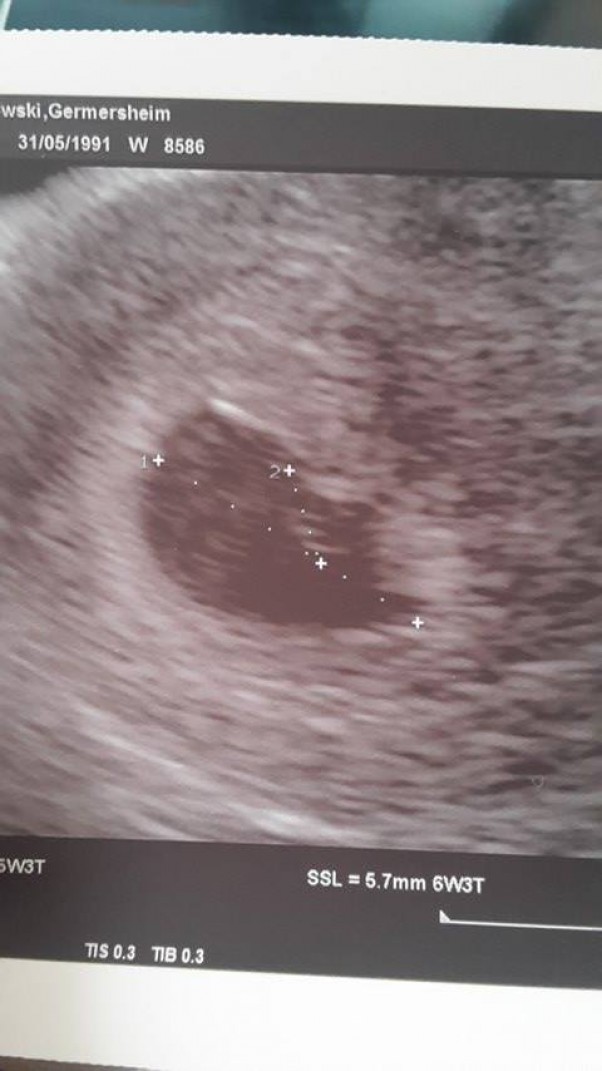

no i nasze szczęście znowu urosło :) teraz ma 5,7 mm i dobrze się rozwija. następna nasza wizyta odbędzie się 9 czerwca :). mamusia czuje się świetnie a tatuś chyba jeszcze bardziej :) pozdrawiamy